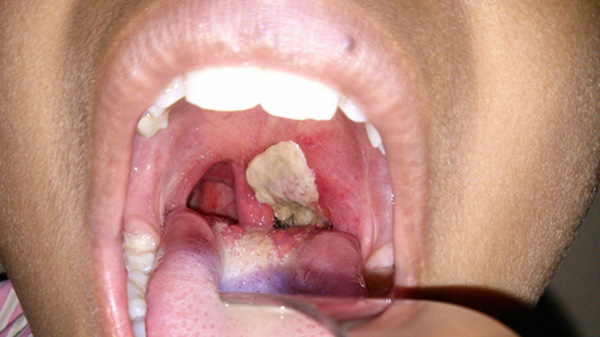

Bạch hầu là một chứng nhiễm trùng nghiêm trọng có ảnh hưởng tới niêm mạc cổ họng và mũi. (Ảnh minh họa: Internet)

Bạch hầu là một chứng nhiễm trùng nghiêm trọng có ảnh hưởng tới niêm mạc cổ họng và mũi. Nếu không được điều trị kịp thời, bệnh bạch hầu có thể gây thiệt hại trầm trọng cho thận, tim và hệ thần kinh. Ít nhất 3% trường hợp trong tổng số bệnh nhân bị bạch hầu sẽ tử vong.

Với bệnh bạch hầu họng thông thường, thời kì nung bệnh thường kéo dài 2-5 ngày mà không có triệu chứng lâm sàng. Khi chuyển sang thời kì khởi phát, các triệu chứng phổ biến thường bao gồm: sốt nhẹ (38-38,5 độ C), sổ mũi 1 hoặc 2 lần, niêm mạc họng đỏ, kém sáng hơn. Xuất hiện những chấm trắng mờ và mỏng, hạch dưới hàm sưng to và đau. Khi chuyển sang thời kỳ toàn phát (2-3 ngày sau), người bệnh cảm thấy khó nuốt, nuốt vướng, đau cổ họng, người mệt mỏi xanh xao, có thể xuất hiện thêm triệu chứng có giả mạc ở mặt sau hoặc 2 bên thành họng, có màu trắng ngà, xám hoặc đen. Giả mạc này thường dai, dính và dễ chảy máu.